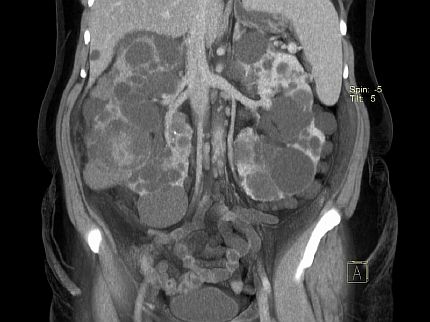

Поликистозное заболевание почек – генетическая болезнь, проявляющаяся в образовании и развитии большого количества кист, которые со временем атрофируют орган и делают его безжизненным.

Растущие кистозные образования, наполненные жидкостью, приводят к увеличению размеров почек и их структурному изменению. Большие почки вызывают боли в спине и сбоку, может возникнуть кровотечение. Если киста разорвётся, больной испытывает нестерпимую боль. Иногда наблюдается моча с кровью. Поликистоз может привести к камням в почках, воспалительным процессам. Может появиться озноб, повысится температура тела. При запущенной болезни часто повышается артериальное давление.